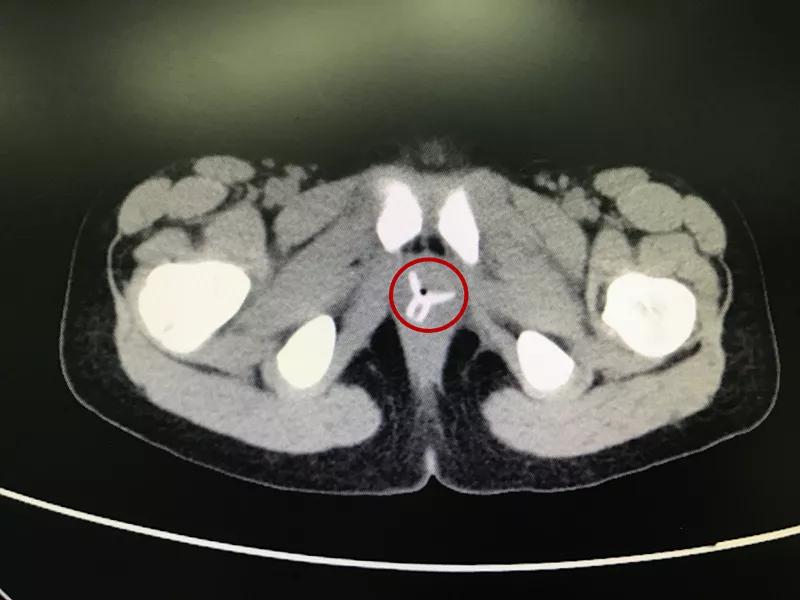

一年后再次就诊,CT结果出来后发现楚楚的阴道内有一个“Y”形的异物,这应该就是“会阴红肿,分泌物增多”的罪魁祸首。

随后在家长的再三询问下,楚楚想起去年暑假,自己和小伙伴玩“医生病人过家家”游戏时,小伙伴曾将一个小吸盘从她的*体下**塞入,但她事后并没有告诉家人。也就是说,异物已经在楚楚体内待了将近一年。